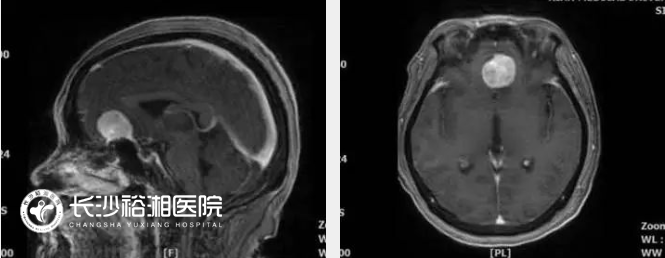

顱底腦膜瘤專指位于顱底部位的腦膜瘤,根據(jù)部位可以分為前顱底腦膜瘤、中顱底腦膜瘤和后顱底腦膜瘤,臨床上常常包括嗅溝腦膜瘤、鞍結(jié)節(jié)腦膜瘤、前床突腦膜瘤、蝶骨嵴腦膜瘤、巖斜區(qū)腦膜瘤和枕骨大孔腦膜瘤等。由于位置深,累及或包裹鄰近的基本神經(jīng)血管結(jié)構(gòu)(如關(guān)鍵動(dòng)脈、顱神經(jīng)、靜脈和靜脈竇),并且在診斷前通常體積較大,顱底解剖復(fù)雜,血管神經(jīng)走行復(fù)雜。盡管多模式治療策略隨著立體定向和分割放療的進(jìn)展而不斷發(fā)展,但手術(shù)切除仍然是治療這些腫瘤的主要方法。然而,從技術(shù)角度來看,切除這些腫瘤是具有挑戰(zhàn)性的,需要幾種顱底手術(shù)方法的專業(yè)知識(shí),這些手術(shù)方法依賴于充分的骨切除,最大限度地減少腦回縮,并尊重附近的神經(jīng)血管結(jié)構(gòu)。顱底外科組長(zhǎng)期從事顯微外科微創(chuàng)手術(shù),對(duì)于顱底各類腫瘤具有豐富的微創(chuàng)治療經(jīng)驗(yàn)。